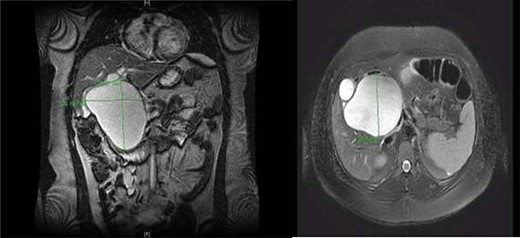

CC with mass effect on liver and duodenum in coronal (A) and axial (B) views.

A right upper quadrant abdominal ultrasound was obtained which showed that the gallbladder wall was 3 mm, an obscured common bile duct (CBD), and a cystic lesion communicating with the CBD and a large gallbladder cyst (Fig. 2). A contrast MRI with magnetic resonance cholangiopancreatography (MRCP) of the abdomen revealed marked fusiform dilatation of the extrahepatic CBD measuring 8.8 cm anterior–posterior x 10.9 cm transverse x 12.7 cm craniocaudally, mild-to-moderate central intrahepatic bile duct dilatation and posterior displacement of the patent main portal vein due to associated mass effect (Fig. 3). Based on the image findings the diagnosis of a CC was made. The type, however, could not be definitively diagnosed as the cyst could be a large type I CC with resultant upstream intrahepatic ductal dilatation versus a type IVa CC with associated mild to moderate central intrahepatic biliary ductal dilatation. Upon review of the images, labs, assessment of the patient, she was scheduled for resection of the extra hepatic bile duct and choledochal cyst with planned Roux en y hepaticojejunostomy. Intraoperatively, she was found to have a massive 20 cm type I choledochal cyst (Fig. 4).